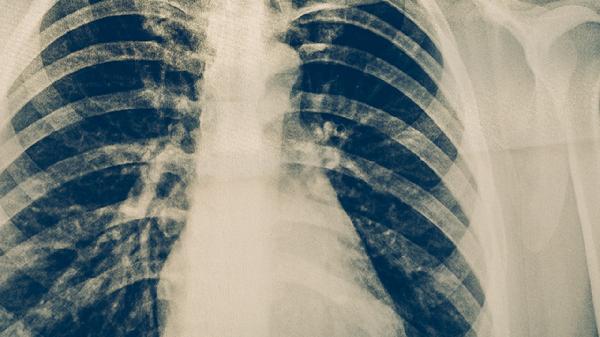

家庭成員需全程佩戴口罩并定期進(jìn)行胸部X線檢查。保持居家環(huán)境干燥清潔,患者用品單獨存放。督促患者按時復(fù)診,治療期間避免前往人群密集場所。注意觀察咳嗽、發(fā)熱等癥狀變化,若痰中帶血或呼吸困難需緊急送醫(yī)。合理搭配膳食的同時,可適當(dāng)進(jìn)行散步等低強度運動增強體質(zhì)。